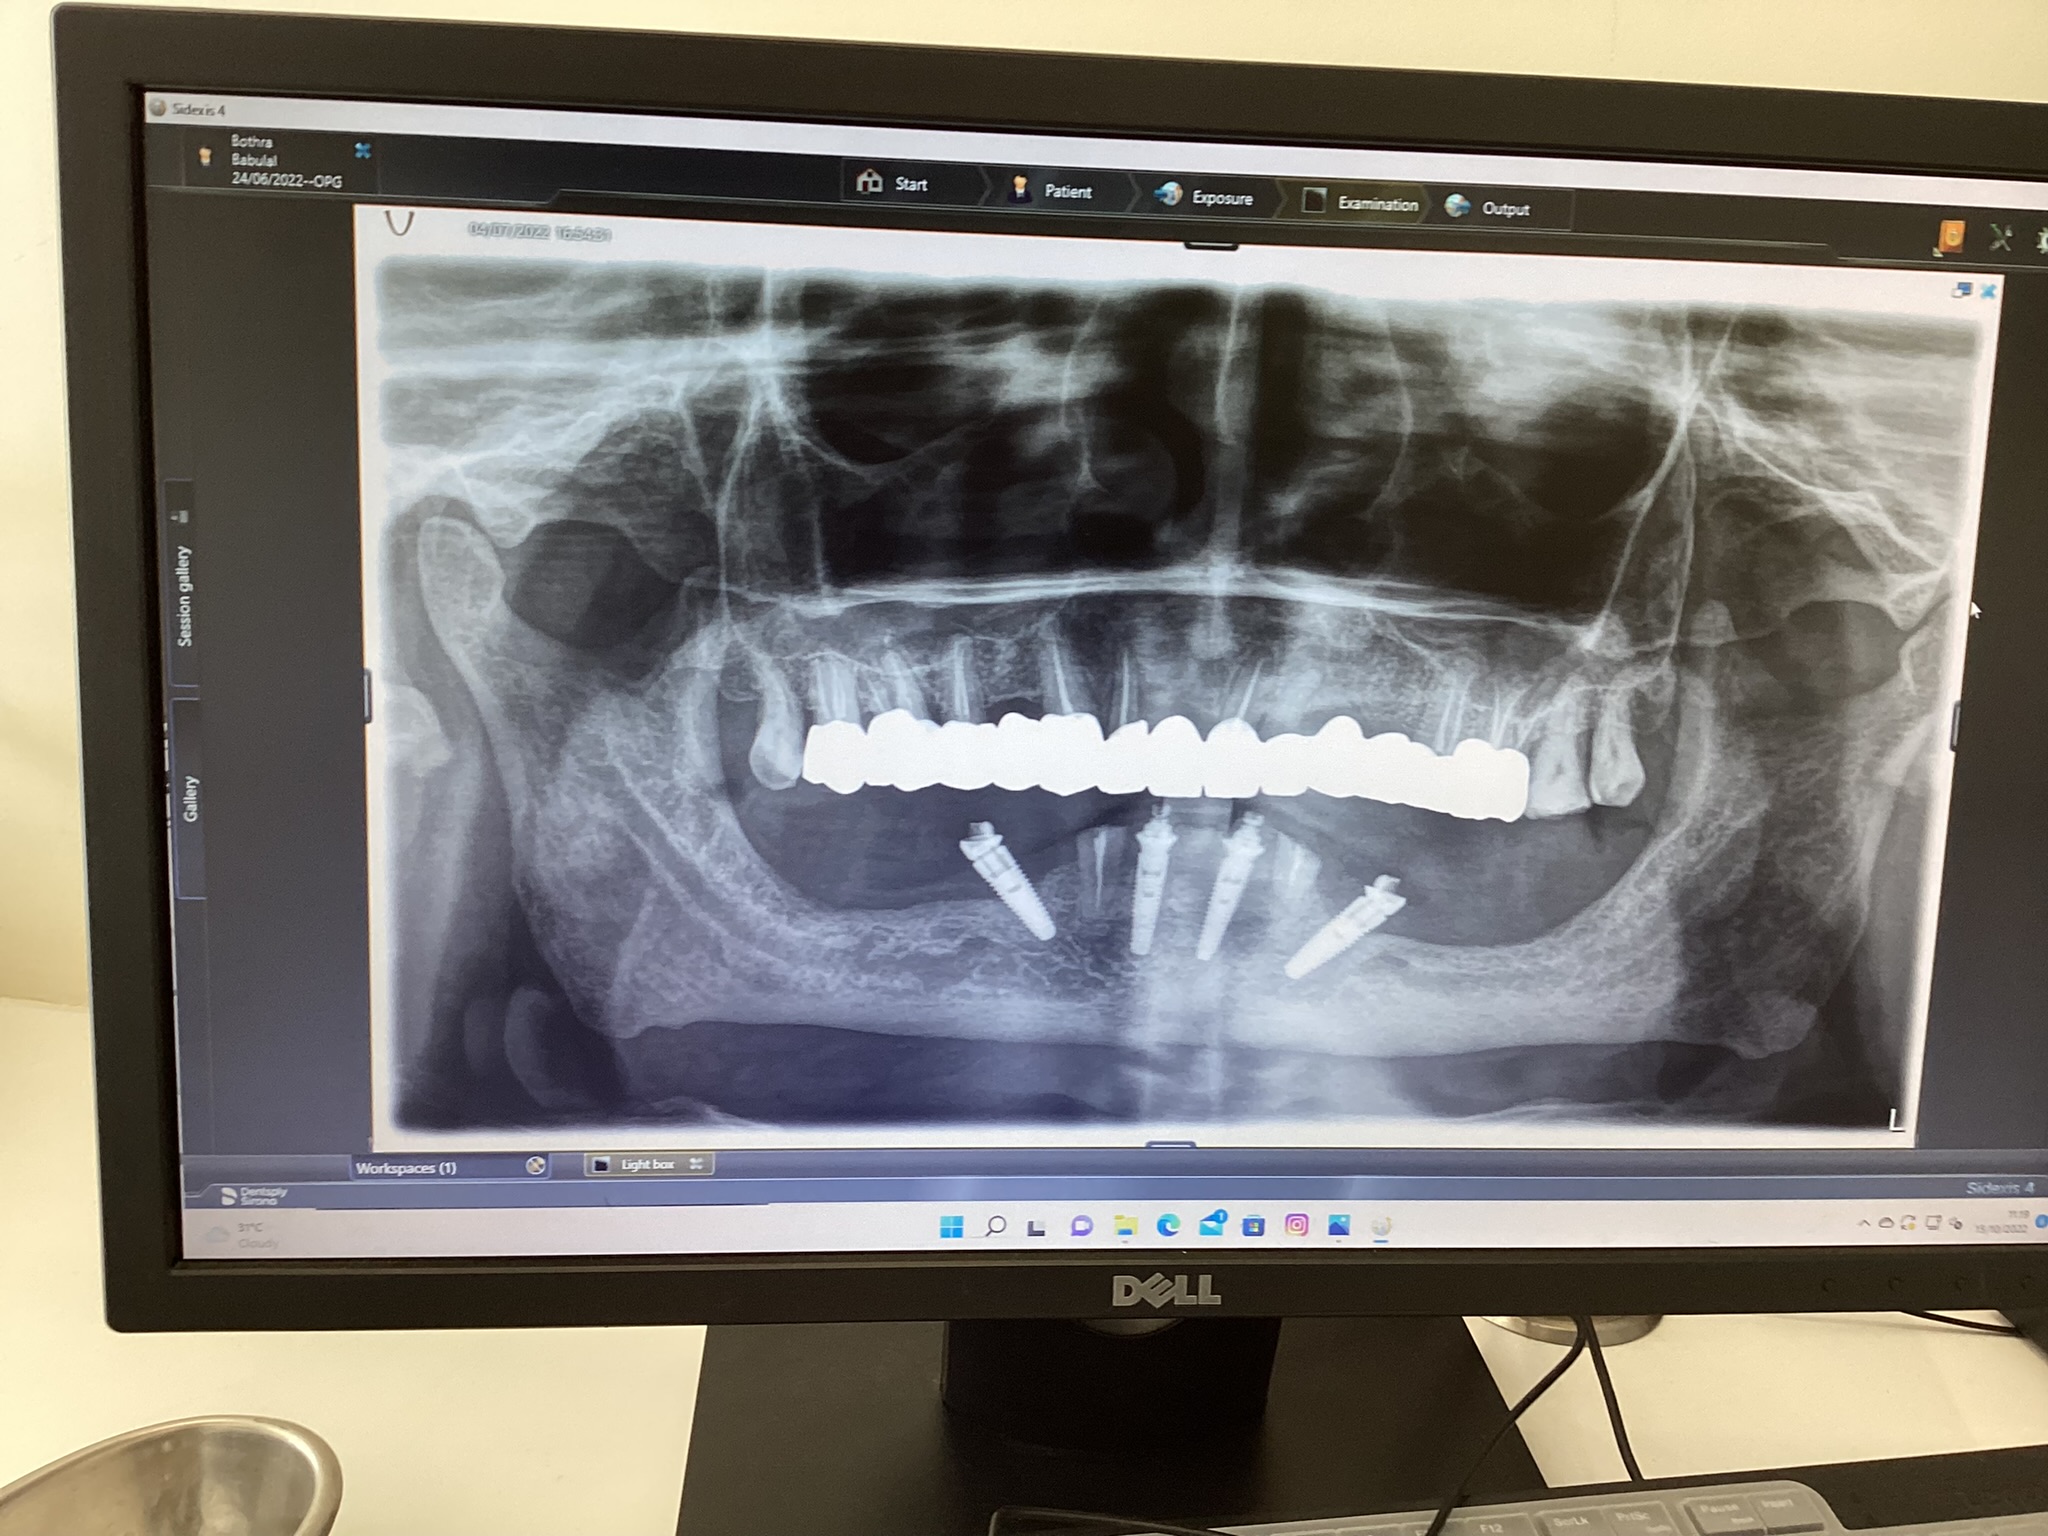

The clinic is equipped with the latest dental technologies to ensure that every dental check-up is thorough and accurate. Digital X-rays, intraoral cameras, and advanced diagnostic tools help in identifying even the smallest issues during the dental examination.

In some cases, X-rays may be needed to get a clearer view of your teeth, roots, and jawbone. These images help in identifying hidden problems like impacted teeth, bone loss, or infections that might not be visible during the initial examination.

In addition to routine dental check-ups, Dentasia offers specialized dental examinations for specific needs: Orthodontic Check-ups: For patients requiring braces or aligners, our orthodontic dental check-ups are designed to assess the alignment of teeth and jaw, offering treatment plans to correct misalignment. Dental Implants: For those considering dental implants, we offer specialized check-ups that evaluate your jawbone health and determine the best course of action for implant placement. Senior Citizens: We provide dental checks tailored to senior citizens, focusing on age-related issues such as gum recession, tooth wear, and dental prosthetics. Click here to know more about dental implants and bridges.